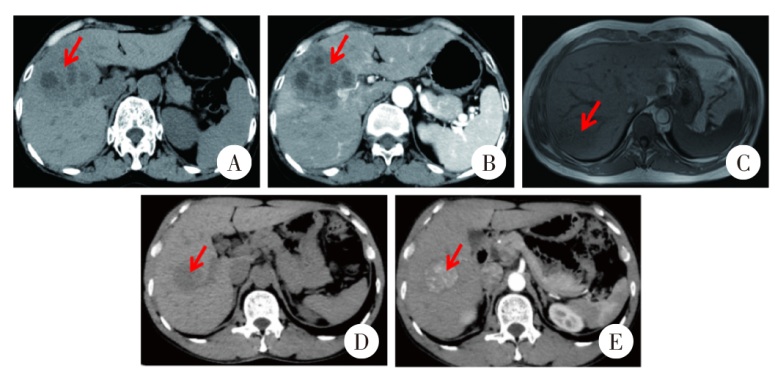

Fig. 1

Comparison of abdominal imaging features between fasciolosisis (A, B, C) and primary liver cancer (D, E) patients A: In the venous phase of abdominal CT, multiple quasi-circular hypodense lesions are visible in the right hepatic lobe, distributed in a clustered pattern; B: In the arterial phase of abdominal CT, hepatic lesions demonstrate no significant enhancement; C: In abdominal magnetic resonance imaging, hepatic segments 6 and 7 demonstrate patchy hypointense lesions; D: In the venous phase of abdominal CT, nodular hypodense lesions are observed in the right hepatic lobe; E: In the arterial phase of abdominal CT, significant enhancement is observed within the lesions in the right hepatic lobe.